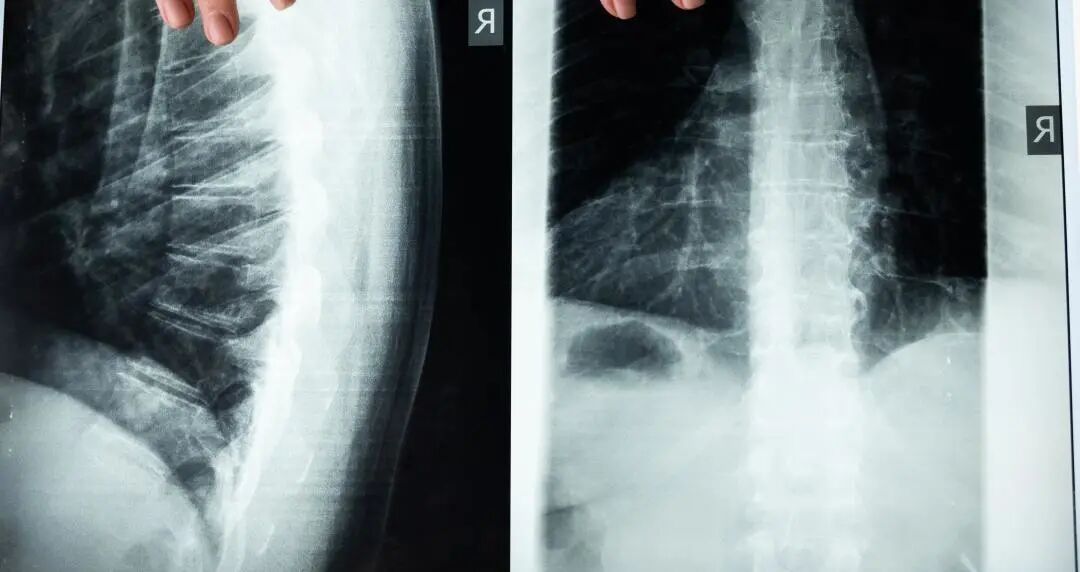

目前,骨科集采已经在多地进行了“模拟预演”。从已公布中标结果来看,安徽骨科脊柱平均降幅53.4%,最高降幅95%;骨科关节类平均降幅81.97%。最近由淄博、青岛等组成山东省七市组成的采购联盟更是砍出了“骨折价”,最高降幅达94%,平均降幅67.3%。

所以面对国产化还不成熟的关节产品,国家集采可能降幅不会像冠脉支架那么大。另一方面,也有人认为,骨科企业的价格底线会进一步击穿。目前国产髋关节平均出厂价为2900元/套,进口髋关节平均价格为1.1万/套;国产膝关节平均出厂价为4800元/套,进口膝关节产品平均价格为1.2万/一套。